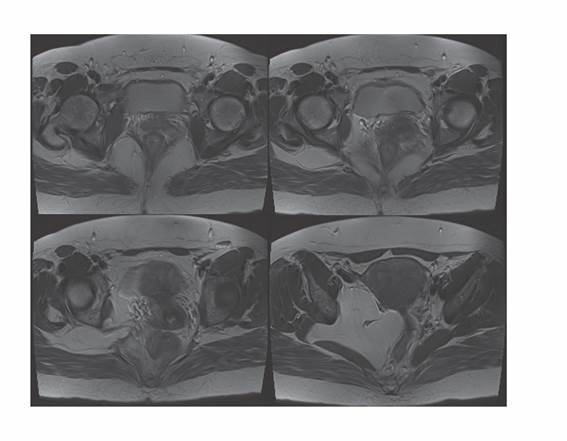

En RM pelviana de octubre del 2022 se apreció imagen ocupacional de aproximadamente 9,5 x 10 cm en hemipelvis derecha con alta intensidad de señal en secuencias potenciadas en T1 y T2 sugiriendo tumoración de estirpe grasa con efecto masa sobre estructuras intraabdominales, desplazando el recto, cuello uterino y vagina hacia el lado izquierdo (Figura 2 y Figura 3). En su porción lateral se introducía ampliamente por escotadura ciática derecha. Se procedió a la realización de punción aspiración con aguja fina, con abordaje posterior, bajo control de tomografía axial computarizada (PAAF-TAC) (Figura 4) de masa intrapélvica, obteniendo muestra para estudio histológico. El informe anatomopatológico confirmó tejido de aspecto adiposo maduro, compatible con lipoma por lo que se derivó a consulta de Cirugía.

Figura 2. Serie axial de RM pelvis en T2. Imagen de masa en pelvis derecha que se introduce en agujero ciático derecho.